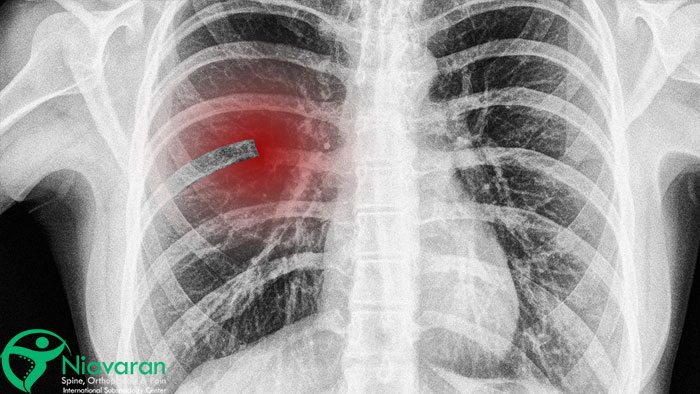

عوارض شکستگی دنده چیست؟

شکستگی استخوان دنده، به خصوص در موارد شدید یا عدم درمان مناسب، میتواند به عوارض جدی و گاهی تهدیدکننده حیات منجر شود. از جمله این عوارض میتوان به پنوموتوراکس (جمع شدن هوا در فضای جنب)، هموتوراکس (جمع شدن خون در فضای جنب)، کبودی یا پارگی ریه، آسیب به قلب و عروق بزرگ، عفونت در محل شکستگی (در موارد شکستگی باز)، درد مزمن قفسه سینه، اختلال در تنفس و کاهش ظرفیت تنفسی اشاره کرد. همچنین در شکستگیهای متعدد دنده، ممکن است قفسه سینه ناپایدار شده و تنفس بهشدت مختل شود که به این وضعیت “قفسه سینه شناور” یا “Flail Chest” میگویند.

آیا شکستگی دنده موجب از کار افتادن ریه میشود؟

شکستگی دنده به خودی خود باعث از کار افتادن کامل ریه نمیشود؛ اما میتواند به آن آسیب بزند. در شکستگیهای ساده، احتمال آسیب جدی به ریه کم است، اما در شکستگیهای پیچیده، خردشده یا جابهجا شده، قطعات شکسته دنده ممکن است به ریه نفوذ کرده و باعث پنوموتوراکس (تجمع هوا)، هموتوراکس (تجمع خون) یا کوفتگی ریه شوند. این عوارض احتمالا تنفس را مختل کرده و در موارد شدید به نارسایی تنفسی منجر شوند.

بنابراین، مراجعه به پزشک پس از شکستگی استخوان دنده، برای بررسی شدت آسیب و شکستگی دنده در ریه بسیار مهم است. تشخیص و درمان زودهنگام میتواند از عوارض جدی جلوگیری کند.